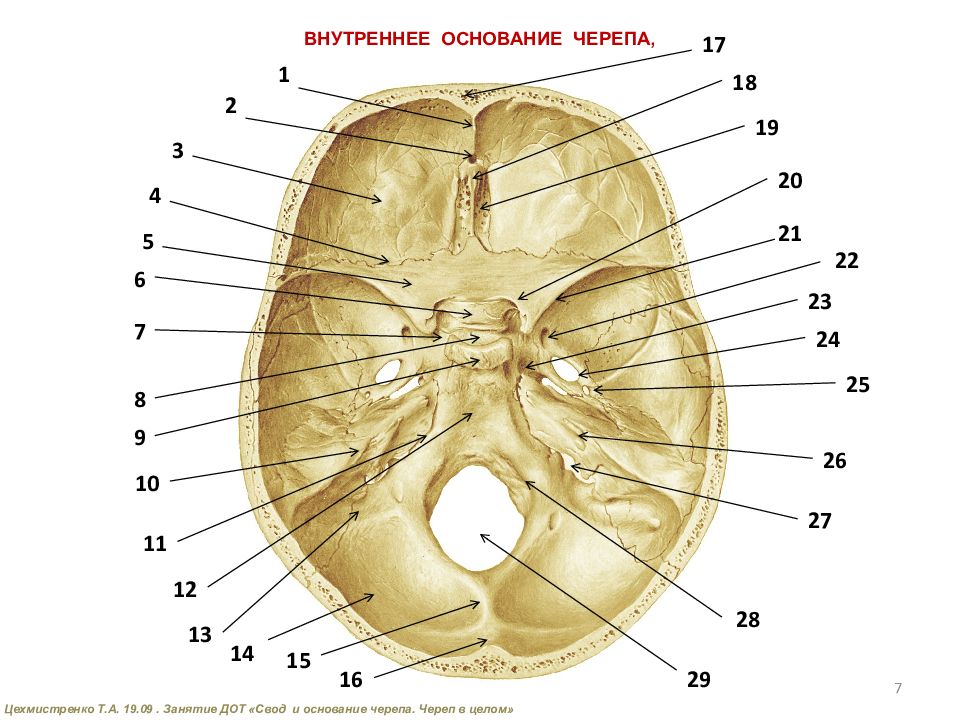

Анатомические детали: Фотографии топографии черепа с нижнего вида